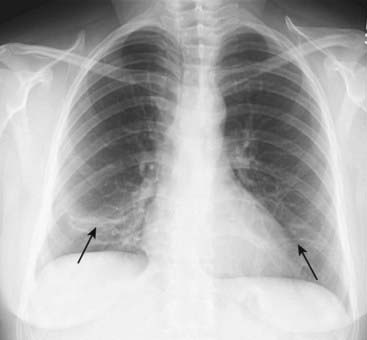

image Chest radiographs should be obtained to aid in the interpretation of the V/Q scan and to rule out another cause of the patient’s symptoms besides pulmonary embolism. In most cases of pulmonary embolism, the initial chest radiograph is normal (Fig. 10).

image

Figure 10 Chest radiograph in pulmonary embolism.

Chest radiographs should be obtained to rule out another cause of the patient’s symptoms besides pulmonary embolism and to aid in the interpretation of the nuclear scan. In most cases of pulmonary embolism, the initial chest radiograph is normal or demonstrates nonspecific findings such as the discoid atelectasis (subsegmental atelectasis) seen in this patient (black arrows).

image If the chest radiograph is normal, then V/Q scanning may be diagnostic. If the chest radiograph is abnormal, a CT-PA is usually performed.